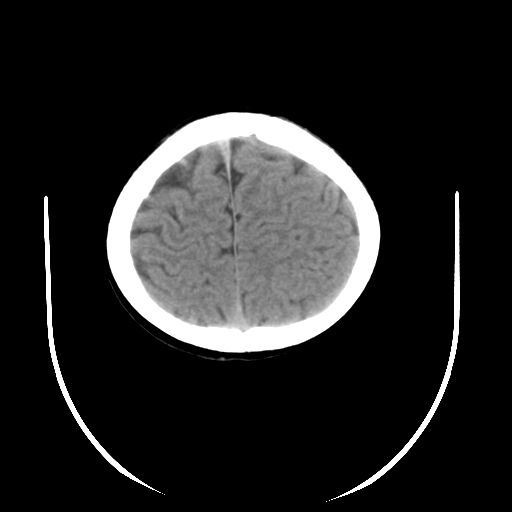

女,6岁,头痛、呕吐一天。